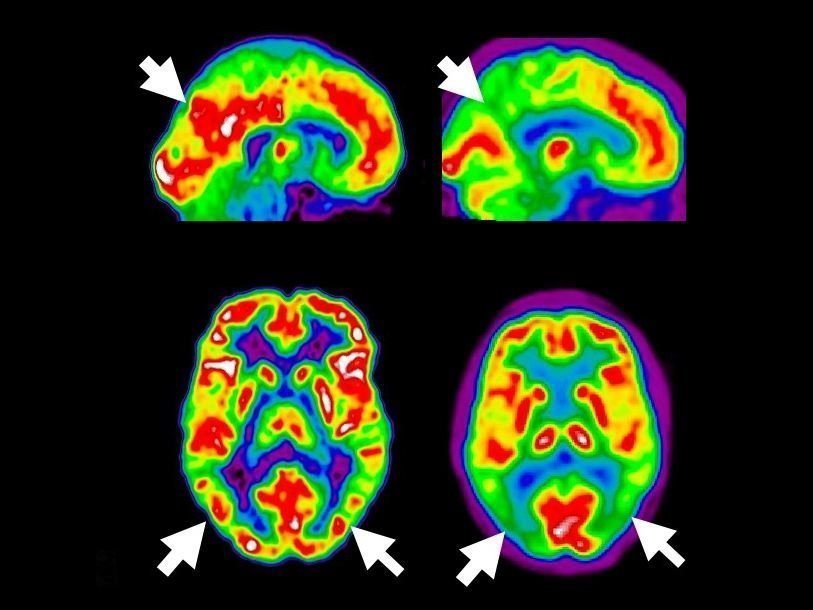

9 привычек, которые вам следует соблюдать, чтобы остановить деменцию и болезнь Альцгеймера, прежде чем она начнется! Очень эффективно! Что такое деменция? Деменция — это не болезнь, но на самом деле симптомы вызывают другие симптомы или травмы, которые воздействуют на